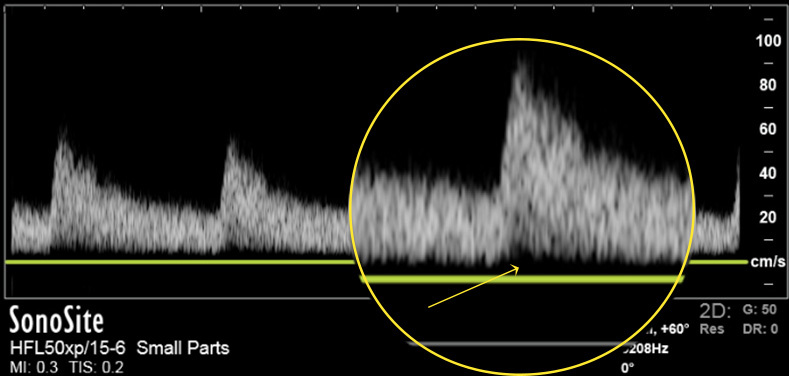

Instrumentation Wall Filter to Baseline Graphic